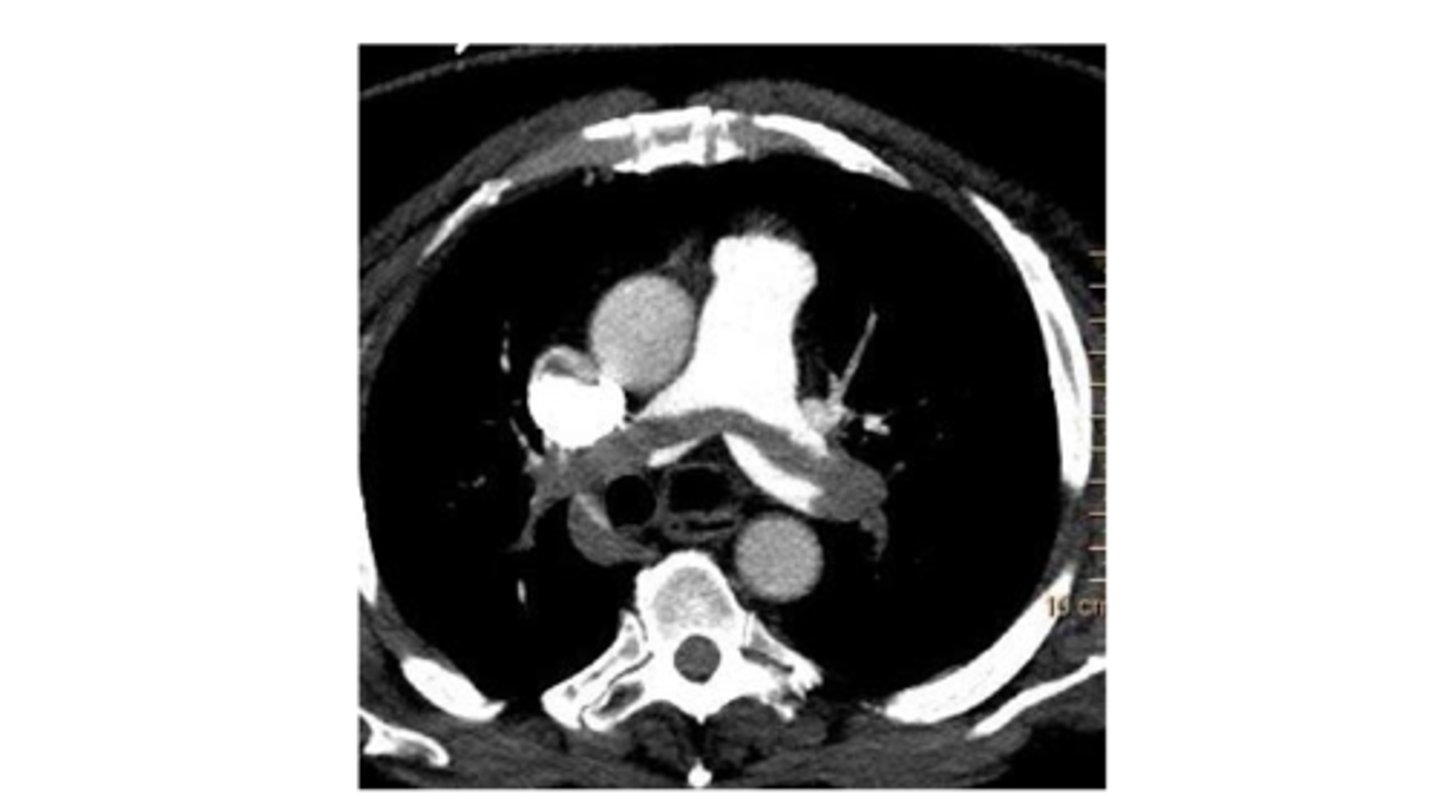

new standard of diagnosis for PE, neg predictive value of 99%. accurate as invasive angiography

CT chest with contrast